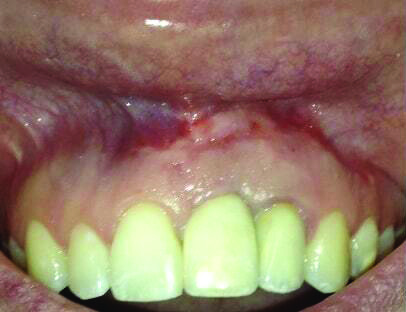

Fig 15 and Fig 16. Case 2: Clinical view (Fig 15) and radiograph (Fig 16) at 12-month follow-up confirming resolution of the peri-implant defect.

Figure 15

The 12-month and 7-year follow-ups for case 2 showed similar improvements with normal soft-tissue healing and bone fill and normal pocket depths at 12 months (Figure 15 and Figure 16) and 7 years post-treatment (Figure 17 and Figure 18) (Table 1).